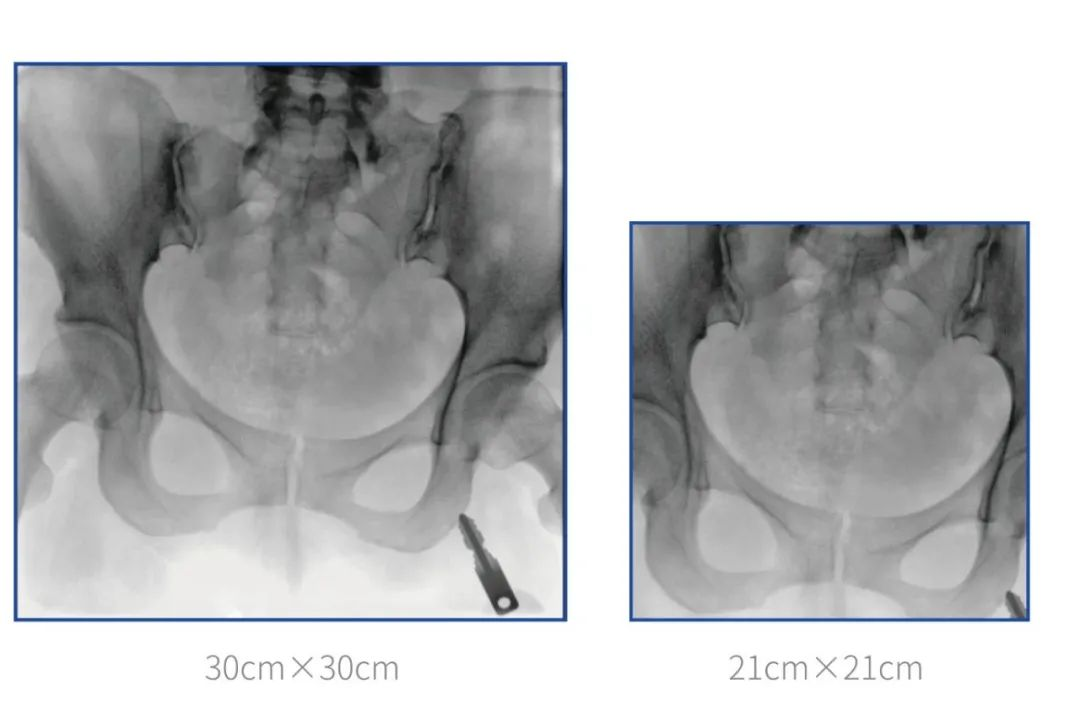

普爱医疗坚持自主研发、持续创新,从临床需求出发,推出了大视野,能够呈现更多图像细节的大平板一体式C形臂。大平板一体式C形臂配置30cm×30cm平板探测器,对于诸如骨盆双侧骨折类型手术或骨盆后环内固定术具有应用优势,一次曝光可获取全部骨折部位影像,可简化曝光流程,提高手术效率!